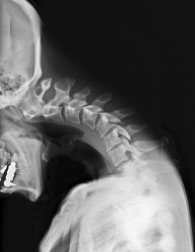

首下がり症候群とは、首の筋肉や骨の構造の問題により首が絶えず前に曲がってしまい、体幹に対して頭部が前屈している状態を指します。

通常、首は頭と共にまっすぐに位置するべきですが、首下がり症では頭が前方に傾いてしまい、姿勢が悪くなります。

首の前傾